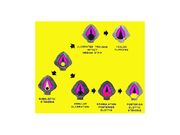

| 08:53, 22 October 2018 | Granuloma.jpg (file) |  |

66 KB | Drtbalu | |